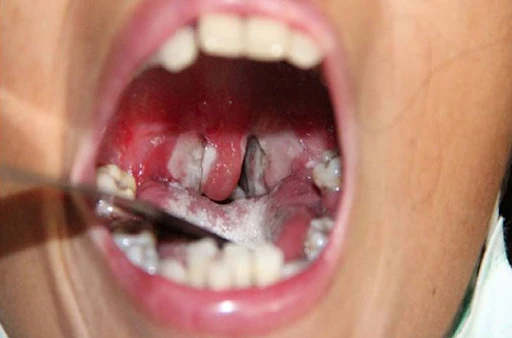

Thể bệnh hay gặp nhất của bệnh bạch hầu là ở đường hô hấp, trong đó 70% là bạch hầu họng.